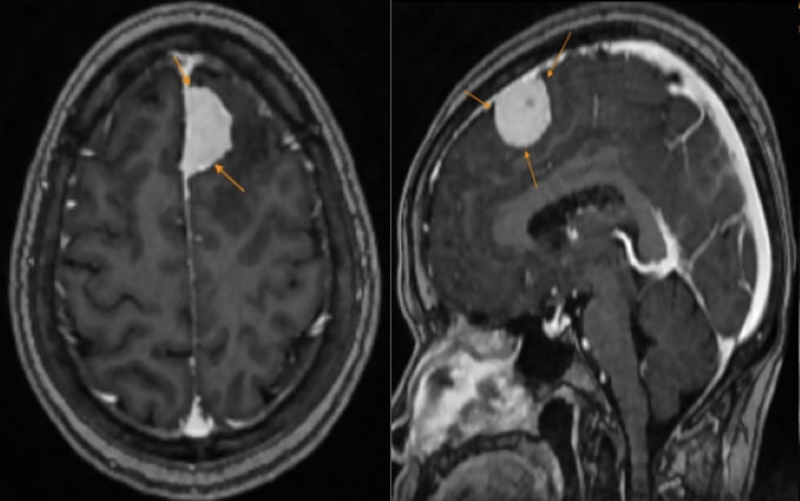

Kết quả trả về khiến cô H. vô cùng bất ngờ: hình ảnh MRI ghi nhận có một khối u lớn vùng trán trái kích thước khoảng 27x15mm, nghĩ nhiều đến u màng não. Sau khi phân tích mức độ tổn thương, các nguy cơ tiềm ẩn và khả năng tiến triển, bác sĩ đã đưa ra tư vấn chuyên môn phù hợp, giúp cô H. định hướng phương án can thiệp kịp thời sao cho an toàn và hiệu quả nhất.

Hình ảnh khối u được phát hiện trên phim chụp MRI